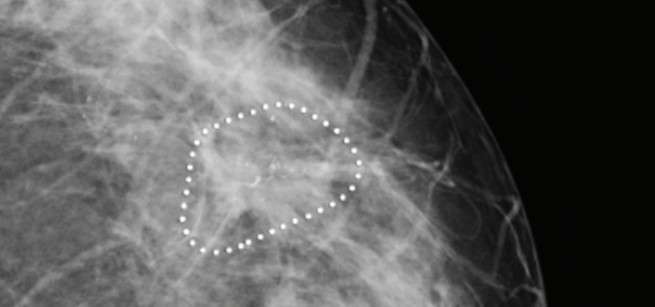

Illustration of suspicious microcalcification clusters using iCAD software on cranio-caudal views of a 74 years old woman with a lump in the right breast. iCAD software identified microcalcification clusters with suspicious morphology